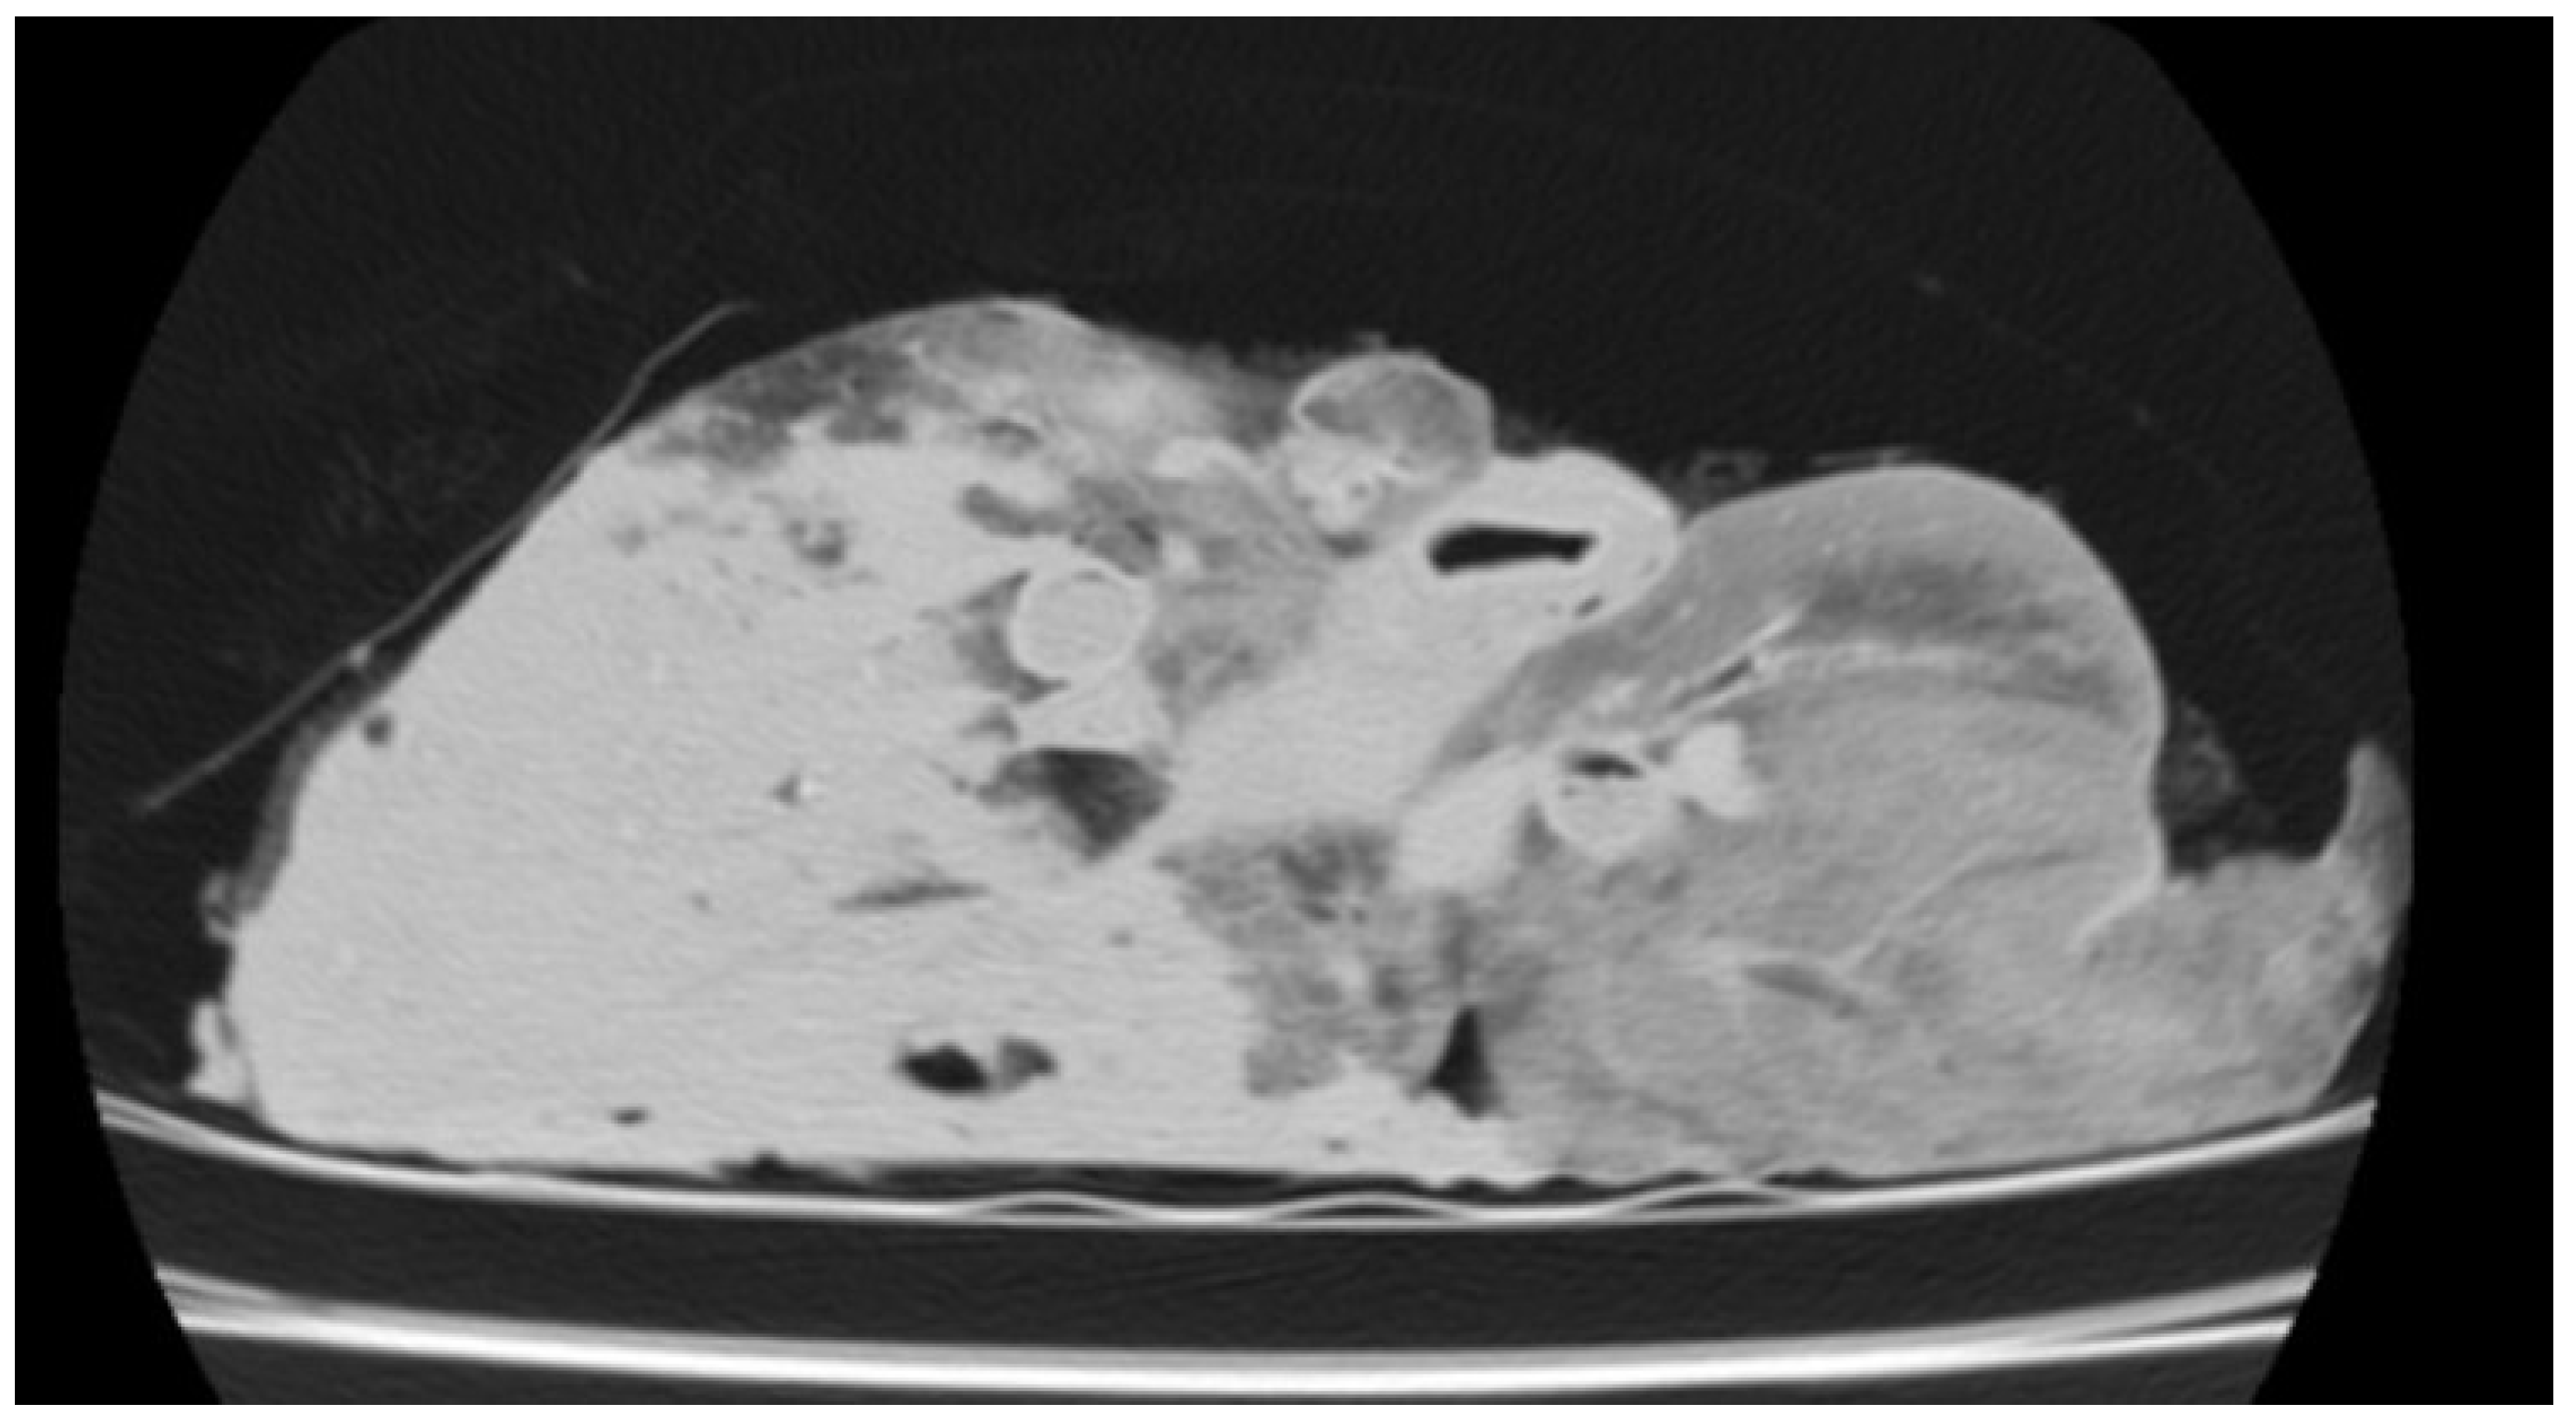

3.3.2. Gangrenous Pneumonia (GN)

| GN | Cranioventral lobes, may extend | 20 to 50 HU (walls), 150 to 600 HU (purulent/necrotic content) | Hypodense necrotic tissue; high HU in purulent/putrid areas |